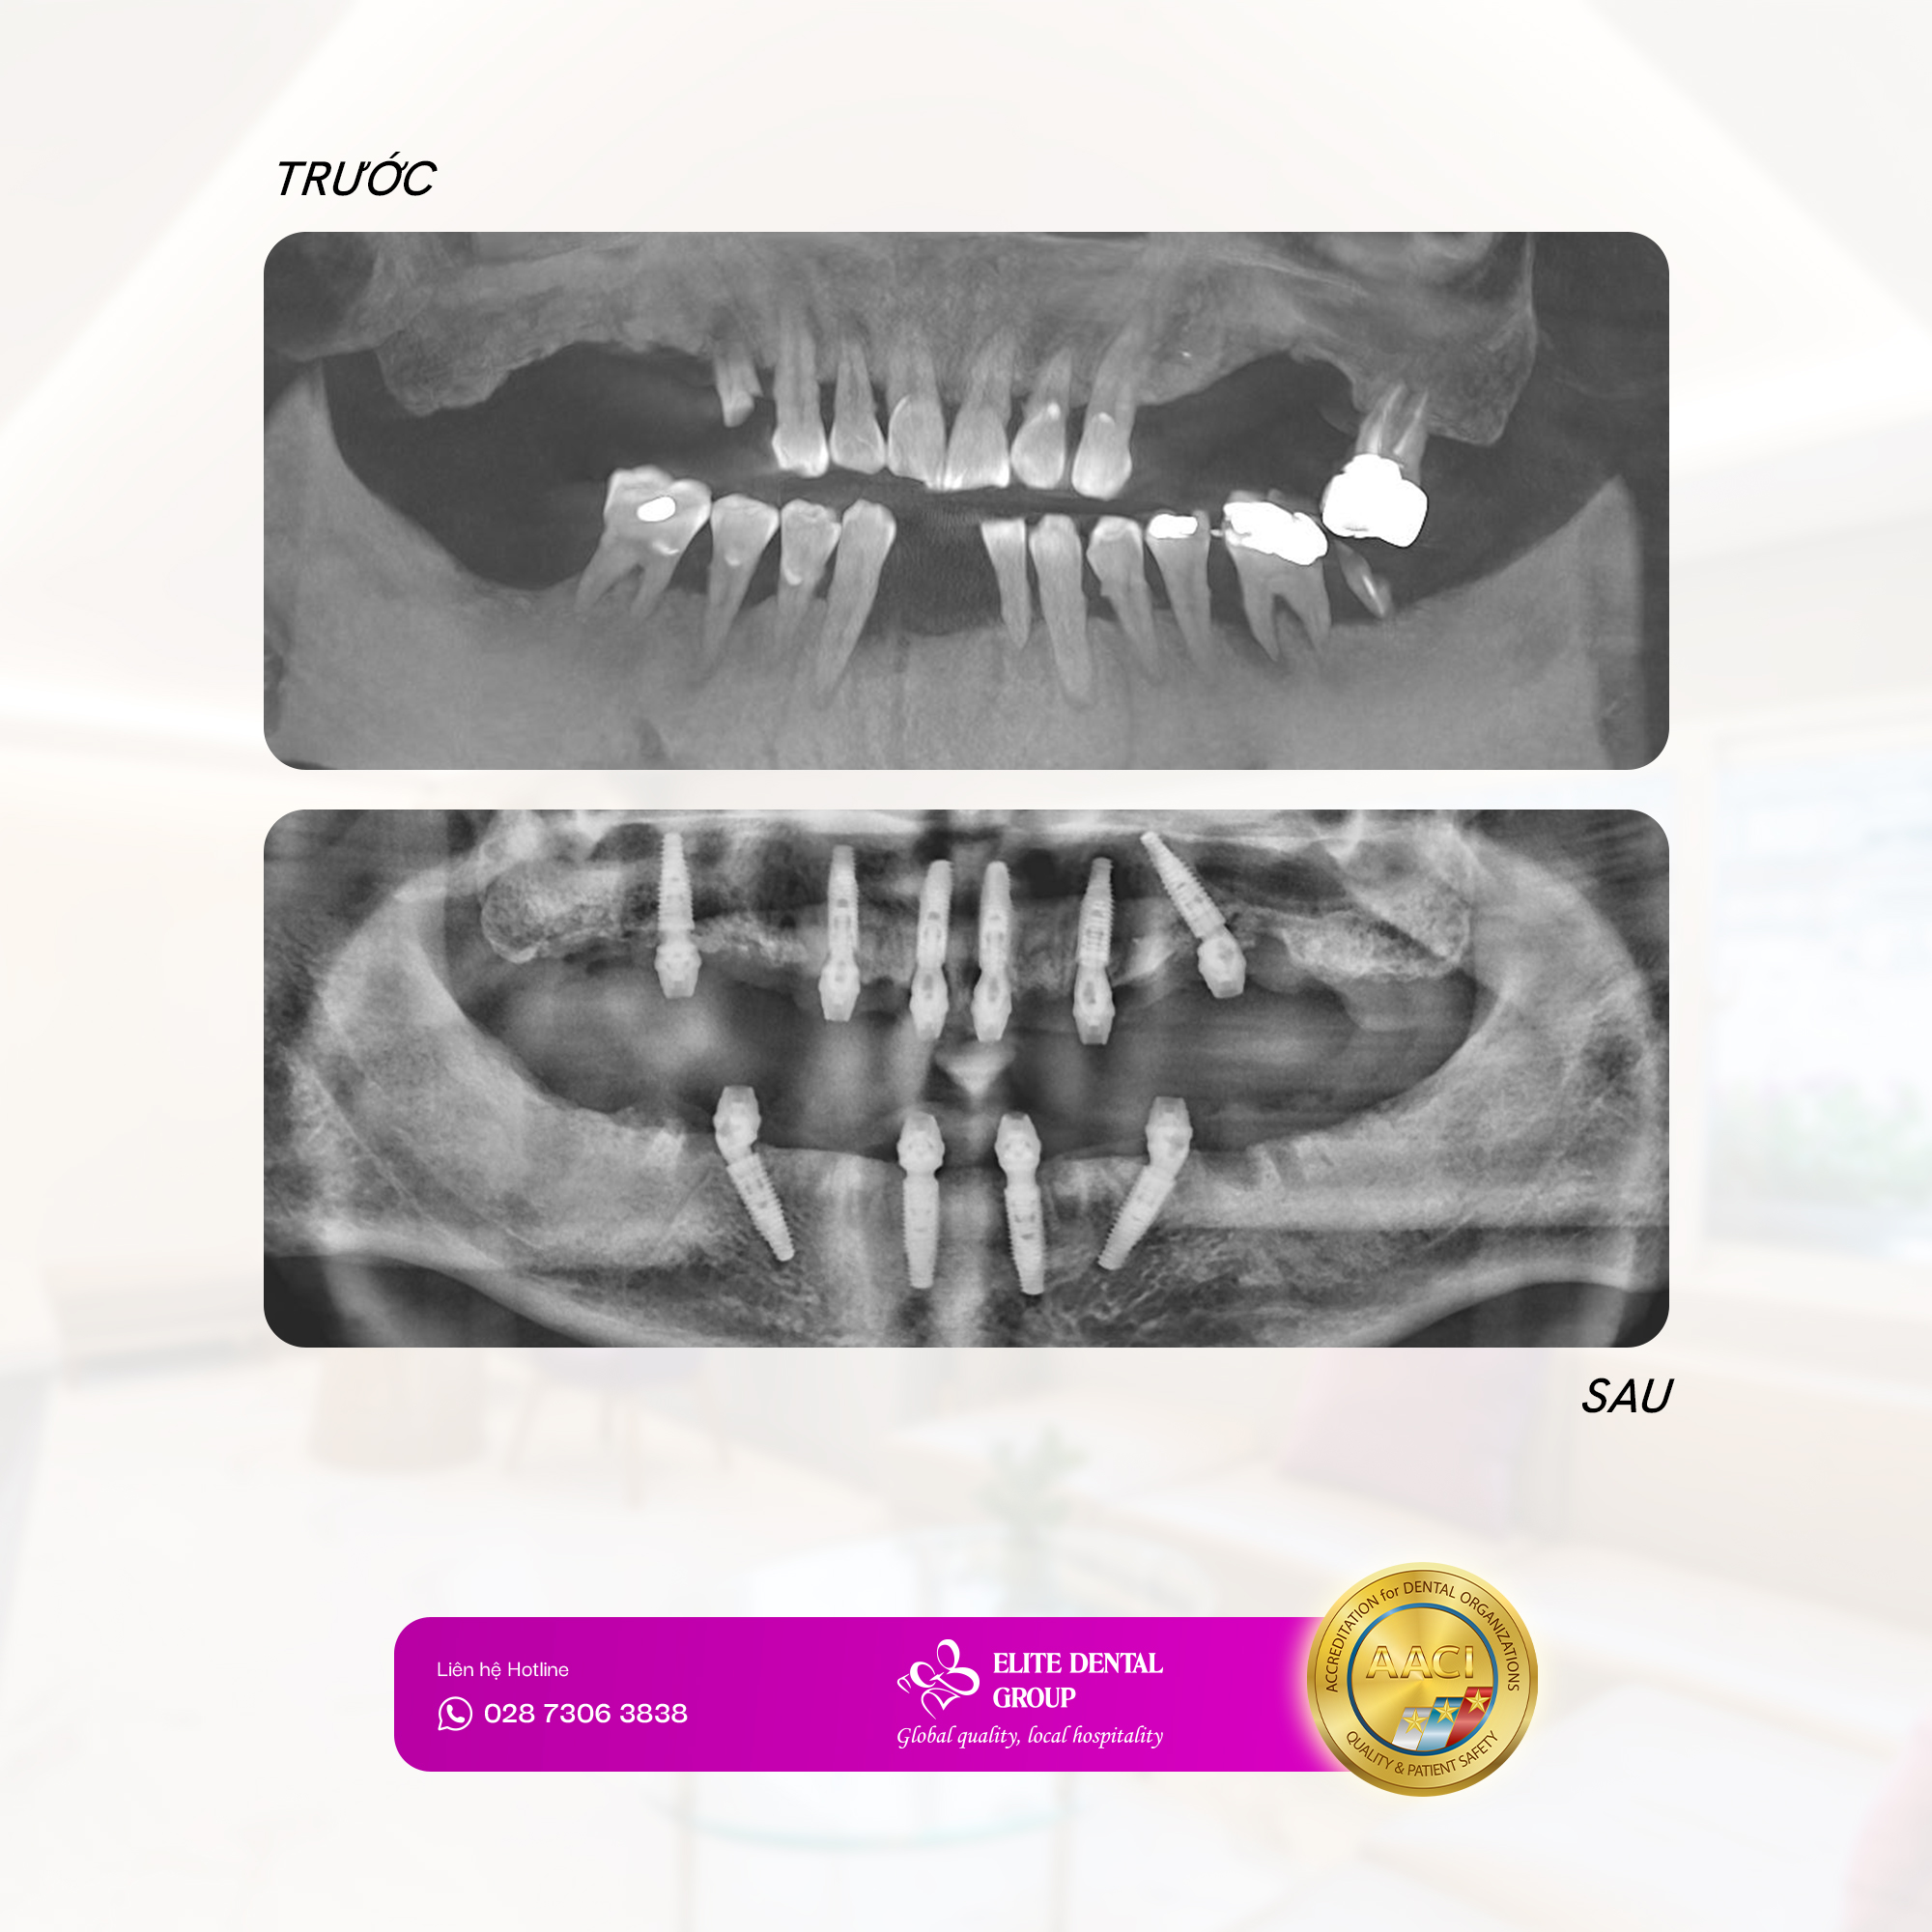

Với kinh nghiệm dày dạn trong cấy ghép & phục hình Implant toàn hàm cùng sự hỗ trợ từ dữ liệu chính xác của công nghệ kỹ thuật số, đội ngũ bác sĩ xác định MẬT ĐỘ XƯƠNG VẪN CÒN ỔN ĐỊNH là một lợi thế lớn, một thời điểm thích hợp để chú Văn Minh nhanh chóng thực hiện điều trị phục hồi răng mất toàn hàm với phương pháp ALL-ON-6 hàm trên và ALL-ON-4 hàm dưới.

Bác sĩ Bảo Phúc – bác sĩ cấy ghép Implant đã lên kế hoạch và thực hiện cấy ghép nhẹ nhàng, kiểm soát chặt chẽ từng vị trí đặt trụ, giúp quá trình phẫu thuật diễn ra thuận lợi và nhanh chóng. Để chỉ sau 2 ngày, bác sĩ Thuỳ An đã có thể tiến hành gắn răng tạm cho chú Minh, khôi phục chức năng ăn nhai tức thì mà không gặp tình trạng sưng đau nhiều như lo lắng ban đầu.